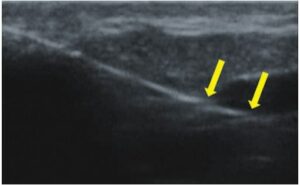

La procédure micro-endovasculaire est une technique endoveineuse qui était principalement utilisée pour le traitement de l’insuffisance des grandes veines du système superficiel et qui a été adaptée pour les veines plus petites. Elle est actuellement utilisée pour fermer les veines réticulaires et les télangiectasies. La procédure consiste à insérer une fibre optique laser stérile et à induire la coagulation des vaisseaux à la suite de l’énergie laser(7,11). Elle nécessite un guidage échographique à haute fréquence. Grâce à l’imagerie échographique, il est possible d’évaluer le trajet et l’anatomie du vaisseau, l’insertion précise de la fibre optique dans les vaisseaux (fig. 7), la coagulation du vaisseau et l’efficacité de la procédure.